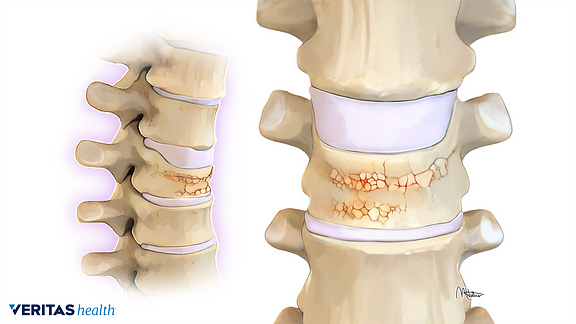

La radiculopatía cervical se produce más comúnmente secundario a una hernación de disco cervical, que puede conducir a la implantación de raíces nerviosas que salen del canal espinal. Los síntomas pueden ser cualquier combinación de dolor, adormecimiento, pérdida de reflejos y / o debilidad muscular. La mayoría de los pacientes generalmente responden al tratamiento conservador en forma de AINES, descanso y inyecciones epidurales de esteroides. Para los casos refractarios de un solo nivel, la disectomía cervical anterior y fusión (ACDF), laminotomía cervical posterior, o la artroplastia de disco cervical (CDA) son el principal del tratamiento.